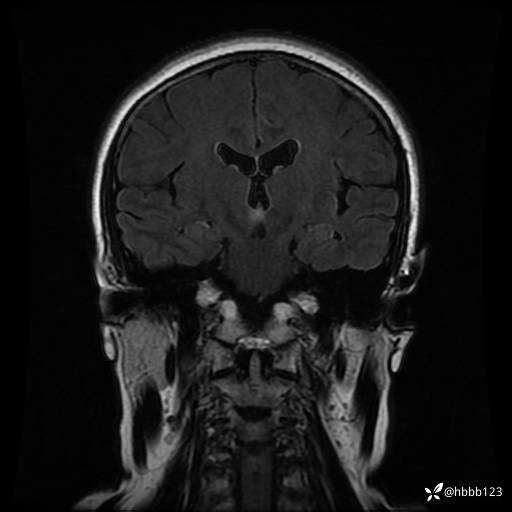

T2 Flair冠状位重建: